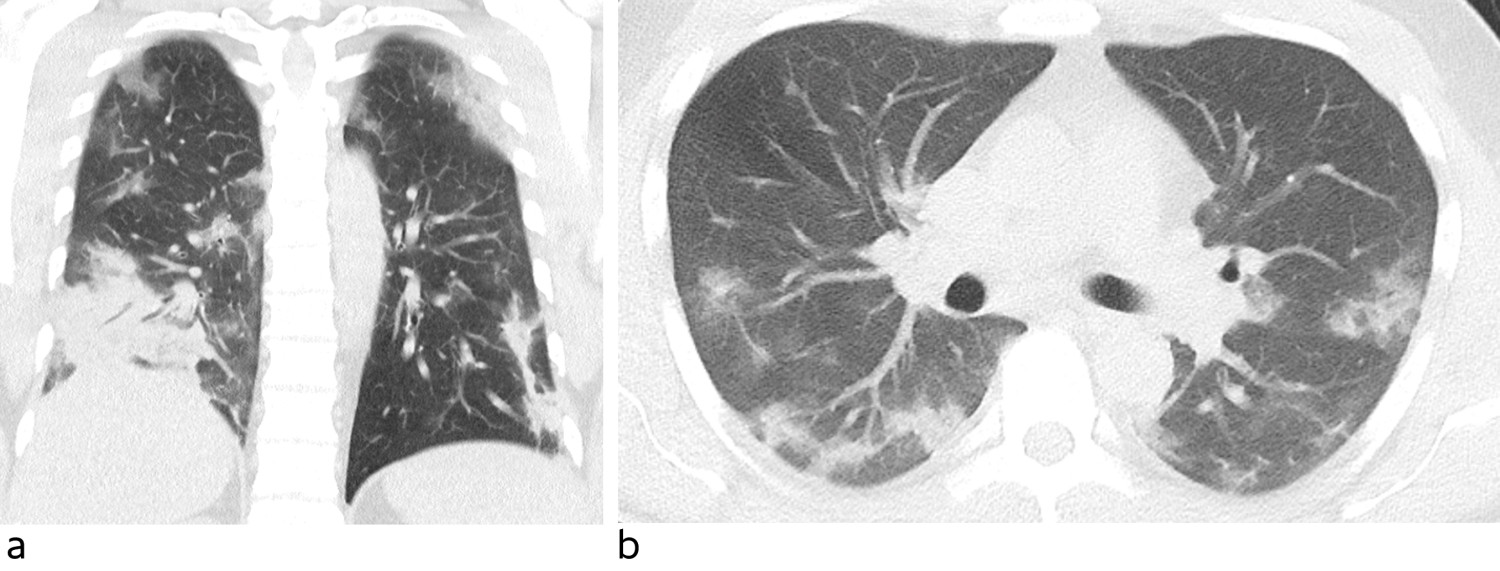

Blodprøver viste hemoglobin (Hb) 12,3 g/dl (13–17), normale leukocytter med normal differensialtelling, senkningsreaksjon (SR) 36 mm (< 13), C-reaktivt protein (CRP) 121 mg/l (< 5), albumin 33 g/l (39–50), laktatdehydrogenase (LD) 349 U/l (105–205), kreatinkinase (CK) 537 U/l (50–400), aspartataminotransferase (ASAT) 47 U/l (15–45) og ferritin 1 192 µg/l (15–350). CT thorax viste rikelig med diffust avgrensede mattglassfortetninger i alle lungelapper, avvekslende med normalt lungeparenkym (figur 1). Apikale forandringer var mest markert perifert. I tillegg var det en konsolidert fortetning basodorsalt i høyre underlapp. Fem og syv dager etter symptomdebut ble det tatt nasofarynksprøve for sars-CoV-2, som ble analysert med polymerasekjedereaksjonstest (PCR). Begge prøvene var negative.

Bronkoskopi med bronkolalveolær skylling er en aeorosolgenererende prosedyre. Ettersom man mistenker at denne prosedyren øker smitterisikoen for personalet, medfører den strengere krav til bruk av smittevernutstyr (7). Indikasjonen må vurderes nøye opp mot gevinst. I vår kasuistikk var det viktig med svar fordi pasienten tilhørte et skipsmannskap og ønsket seg til hjemlandet. I andre situasjoner kan smitterisikoen for personalet og ubehaget det påfører pasienten overgå viktigheten av å utføre prosedyren. Man kan da velge å heller isolere pasienten på bakgrunn av andre funn som gir sterk mistanke om covid-19. Pasienten hadde reiseanamnese som gav mistanke om smitteeksponering samt symptomer (7) og funn ved CT thorax som var forenlig med covid-19. CT-funn har vist seg å ha høy sensitivitet for påvisning av covid-19, opp mot 95 %. Spesifisiteten er dog lav, da andre virus og atypiske infeksjoner kan gi lignende bilde (4, 8, 9). Foruten høyt ferritinnivå ble det kun sett uspesifikke milde avvik på blodprøvene. Vedvarende høyt ferritinnivå har i retrospektive studier vist seg å være et dårlig prognostisk tegn hos covid-19-pasienter (10).